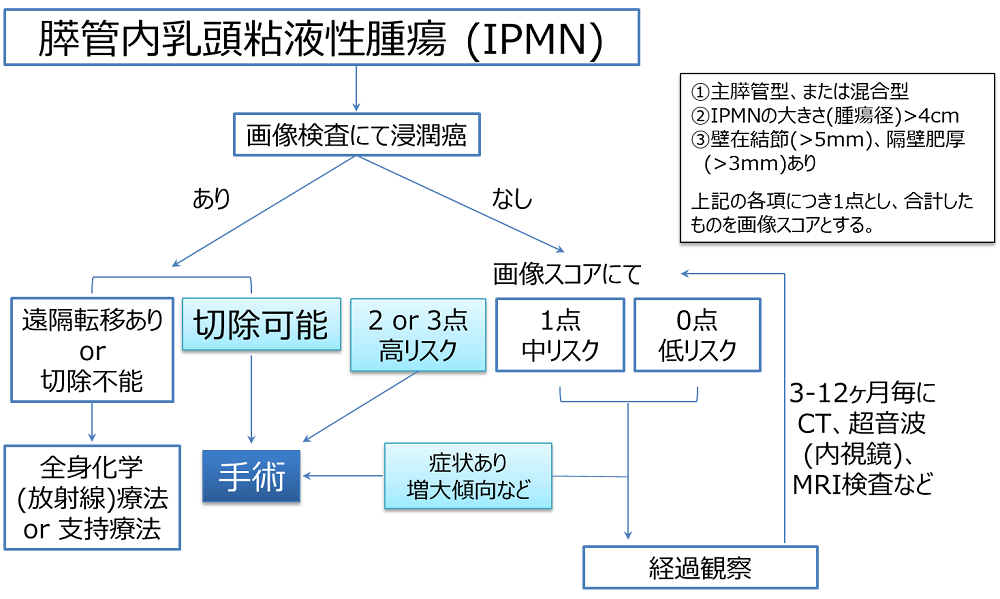

嚢胞(のうほう)とは液体の入った風船のような袋のことであり、膵臓の中もしくはその周囲にできた嚢胞を膵嚢胞と呼びます。 多くの場合、無症状であり、画像診断の進歩により健診などで偶然発見されるケースが増えてきました。 大きさは数㎜程度の小さなものから10cmを超えるものまでさまざまであり、1個だけの場合もあれば複数個認める場合もあります。 がん化の可能性があるIPMN. 膵嚢胞は、腫瘍性嚢胞と非腫瘍性嚢胞に大きく分けられます。 さらに前者は膵管内乳頭粘液性腫瘍(IPMN)、粘液性嚢胞腫瘍(MCN)、漿液性嚢胞腫瘍(SCN)など、後者は膵臓仮性嚢胞、リンパ上皮嚢胞などに分類されます。 膵管内乳頭粘液性腫瘍(IPMN). 膵嚢胞性腫瘍とは?. 膵嚢胞性疾患は、膵臓にできる嚢胞(ふくろ状の)の形態をとる腫瘍の総称で、治療の必要のない良性の腫瘍や炎症性疾患もあれば、悪性リスクのある腫瘍もあり、いくつかの異なった疾患をまとめた疾患概念です。. 近年、膵嚢胞性.

膵のう胞・IPMNがありますと医師に言われたら【患者さん向けの解説】 EUS channel

膵嚢胞性腫瘍(IPMN, MCN, SPN, SCNなど)の外科治療 国立がん研究センター 中央病院